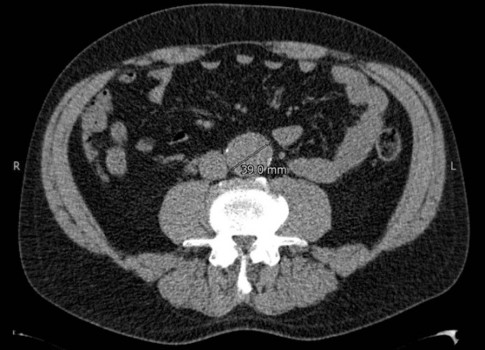

Een 49-jarige man, bekend met hypertensie en sinds enkele jaren gestopt met roken, bezocht in 2013 de spoedeisende hulp in verband met mogelijke nierstenen. Op de CT-scan van het abdomen werd, als toevalsbevinding, een ‘klein’ aneurysma van de buikaorta ontdekt met een diameter van 3,9 cm [figuur 1].

Figuur 1 | Aneurysma van de buikaorta in 2013: diameter 3,9 cm